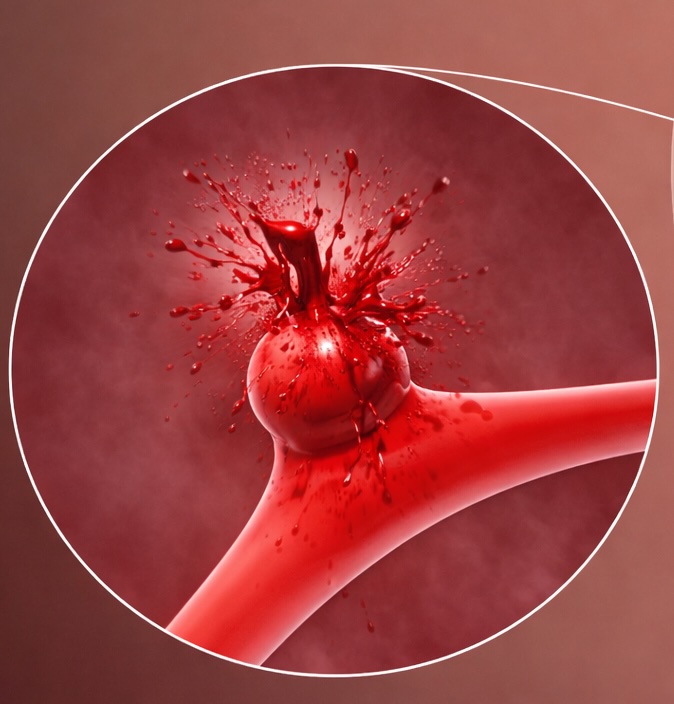

Aneurisma roto

É quando essa “bexiga” se rompe, ou seja, estoura, causando um sangramento dentro do cérebro.

Quando isso acontece, os sintomas costumam ser intensos, principalmente uma dor de cabeça muito forte e repentina, diferente de qualquer dor comum.

O aneurisma roto é uma emergência médica e precisa de atendimento imediato no pronto-socorro.

O mais importante é saber que:

- A maioria dos aneurismas não estoura / rompe

- Aneurisma não roto geralmente não é uma emergência

- Aneurisma roto é sempre uma emergência.

Por isso, ao receber um exame com esse diagnóstico, o mais importante é passar por uma avaliação cuidadosa com o neurologista.

Cada caso é único e depende de fatores como o tamanho da “bolha”, o local onde ela está e as características de cada pessoa.

Com acompanhamento adequado, é possível decidir o melhor caminho com tranquilidade e segurança.